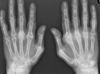

**Psoriatic arthropathy** Pencil in cup X-ray showing some of changes in seen in psoriatic arthropathy. Note that the DIPs are predominately affected, rather than the MCPs and PIPs as would be seen with rheumatoid. Extensive juxta-articular periostitis is seen in the DIPs but the changes have not yet progressed to the classic 'pencil-in-cup' changes that are often seen.

Psoriatic arthritis

Arthritis hands: compare osteoarthritis, rheumatoid arthritis and psoriatic arthritis